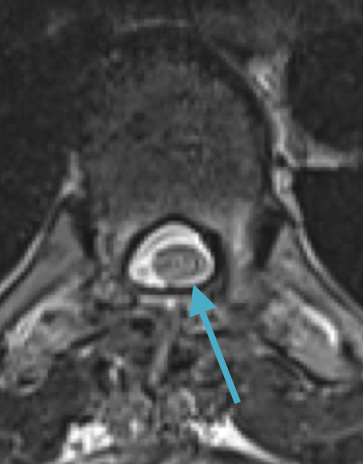

Preoperative MRI T1w demonstrating a large enhancing tumor with severe cord compression